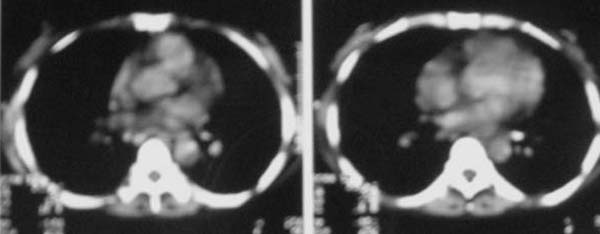

以下是引用zjzjr在2007-9-20 12:29:00的发言:[br]双肺磨玻璃改变,考虑肺水肿.

以下是引用yangzongshan在2007-9-20 18:29:00的发言:[br]两肺毛玻璃样改变,其内可见肺纹理影,无胸腔积液,故考虑肺泡蛋白沉积症

以下是引用276894491在2007-9-20 13:40:00的发言:[br]考虑肺水肿;外源性过敏性肺炎不排除。

以下是引用逸风在2007-9-20 20:45:00的发言:[br]两肺磨玻璃样改变,临床病史短,发热,考虑病毒感染合并右肺代偿性肺气肿.待排肺水肿,病史短,不支持肺泡蛋白沉着症.